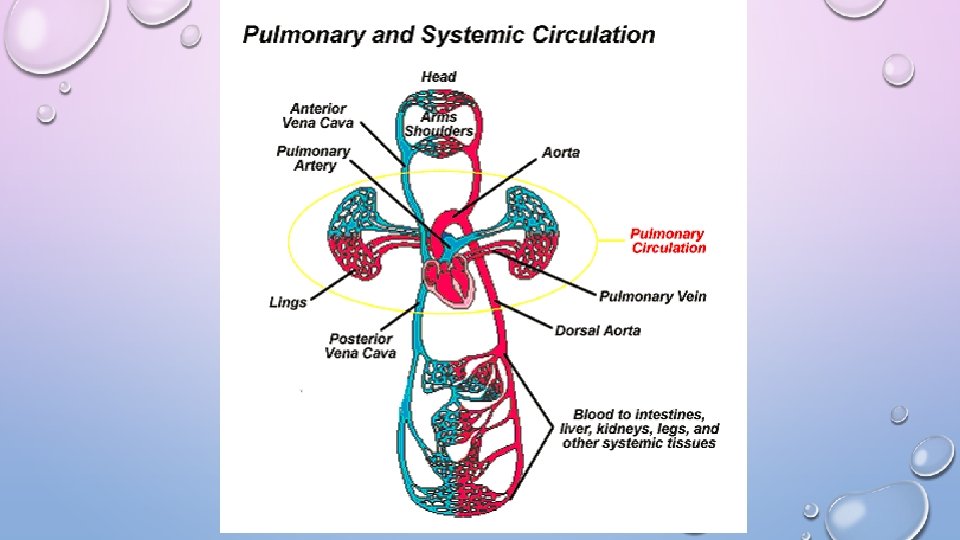

• PULMONARY CIRCUIT- BLOOD FLOW BETWEEN RIGHT SIDE OF THE HEART TO LUNGS AND LEFT SIDE OF HEART • “LUNGS LAP” • SYSTEMIC CIRCUIT- PATHWAY BETWEEN RIGHT AND LEFT SIDES OF THE HEART • “BODY LAP”

THE HEART • CARDIAC MUSCLE WITH INTERCONNECTING CELLS • (INTERCALATED DISCS) • 4 CHAMBERS: • 2 ATRIA (LEFT AND RIGHT) • AURICLES (LOOK LIKE EARS/FLAPS) • 2 VENTRICLES (LEFT AND RIGHT)

THE HEART • MAJOR VEINS • SUPERIOR VENA CAVA AND PULMONARY VEINS • MAJOR ARTERIES • AORTA AND PULMONARY TRUNK